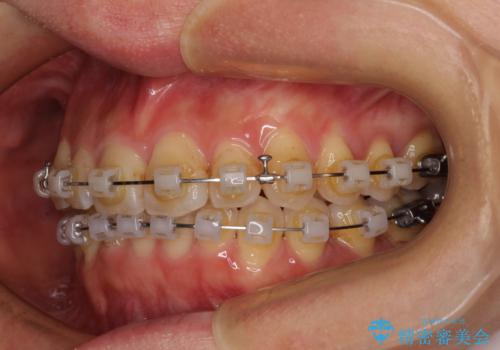

- クリアブラケット

- 上下前歯のデコボコを気にして来院された患者様です。

叢生は軽度で、ワイヤー矯正でもマウスピース矯正でも対応可能な歯列でした。

仕事と小さいお子さんの育児に追われており、インビザラインの自己管理は続ける自信がないとのことで、ワイヤー装置による矯正治療を行うこととしました。

僅か1年間できれいに歯列を整えることができ、患者様には大変満足していただきました。